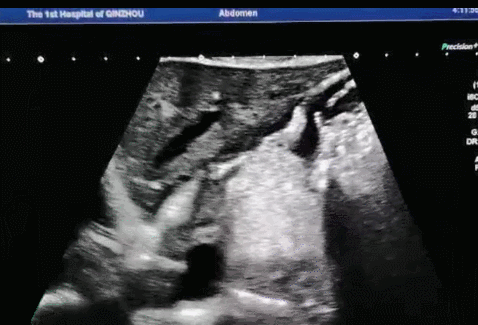

▲口服助影剂充盈后可清晰显示整个的胃全观